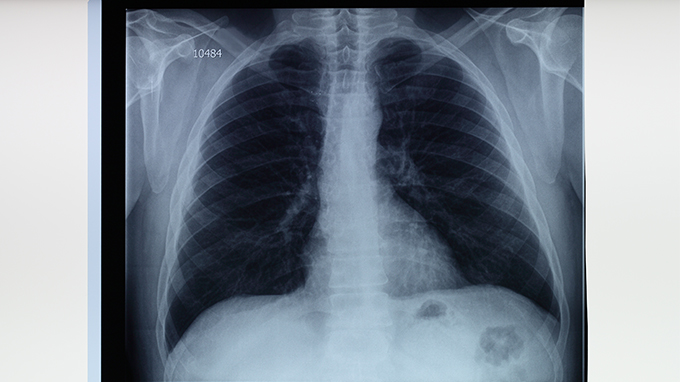

结节状高密度影是癌症吗?有的患者在进行身体检查的过程中,可能会引起肺部结节状,高密度影的现象,这种情况下应该及时进行调理,可以选择支气管镜的方法进行基本的判断,如果出现了结节状,高密度影,可能是由于患有恶性肿瘤导致的这一现象,但是大多数患者都可能是由于患有了炎症引起的高密度影的产生,所以应该进一步进行检查和治疗,如果出现了癌症,应该及早的通过手术来治疗疾病。

1、肺部如果出现了结节状,高密度影的现象,应该进行合理的检测,如果出现了长期没有任何变化,或者变化比较缓慢的情况,可能是由于局部炎症导致这一现象,肿瘤的可能性是非常小的,所以应该进一步进行检测。

2、结节状高密度影的诱因是非常多的,有的患者如果出现了结核样的疾病,或者出现了严重的炎症感染,都可能会导致结节状高密度影的产生,如果出现了恶性或者良性的肿瘤状的病变,也可能会导致结节状高密度影的现象。

3、结节状高密度影的诱发病因是非常多的,所以应该进一步的进行检查和治疗,避免出现恶性肿瘤的产生,平时多注意休息,结节状高密度影的患者,通过使用ct检测或者血液检测的方法来进一步的进行疾病的判断。

结节状高密度影并不一定是癌症,所以应该进一步的检查和确诊,如果出现了恶性肿瘤,最好应该在发病的早期进行合理的治疗,避免出现严重的并发症,甚至会导致癌细胞的扩散和转移,对患者影响非常大。